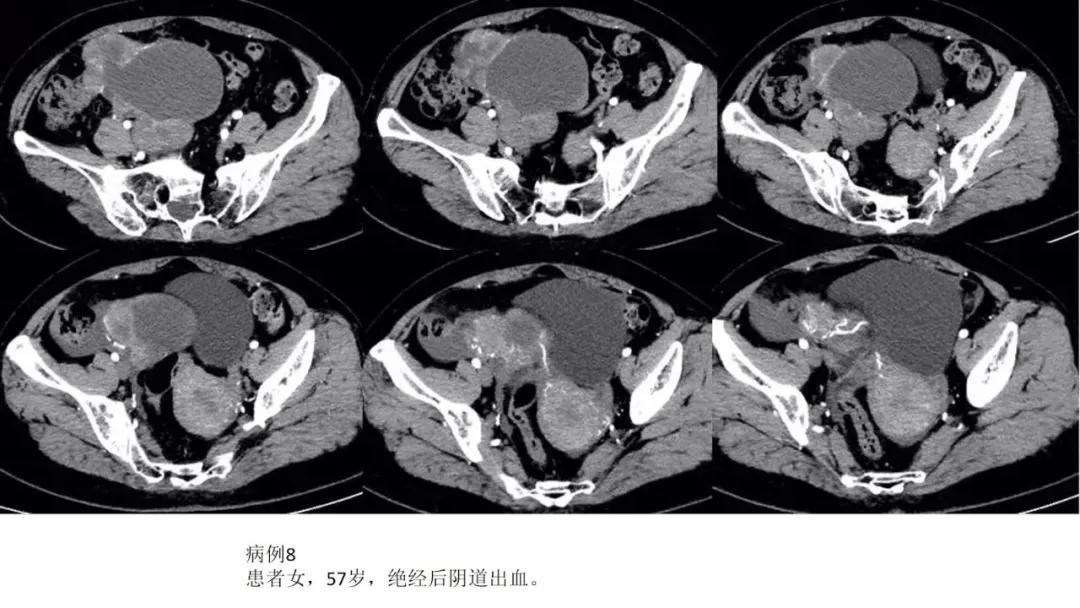

病例10

女,39 岁,体检发现盆腔肿块1月余

CA125:51U/ml

病理:左侧卵巢卵泡膜-纤维瘤